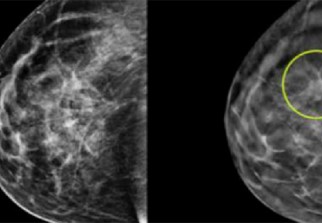

Pour cette étude menée avec 4.805 patientes atteintes d'un cancer mammaire dit HER2 positif, une mutation génétique produisant une protéine qui dope la prolifération des cellules cancéreuses, Roche a combiné son anticancéreux Hercéptine (trastuzumab), la plus ancienne thérapie ciblée, avec une nouvelle molécule du même type, Perjeta (pertuzumab).

Le cancer du sein est le cancer le plus fréquent chez les femmes dans le monde, de 15 à 25% sont de type HER2-positif